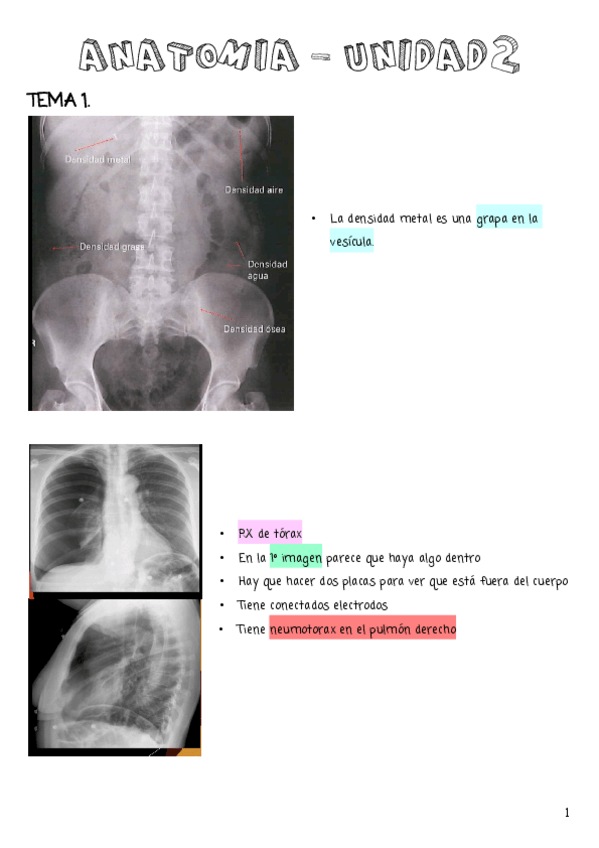

APUNTES UNIDAD 2 (TEMAS DEL 1 AL 4)

He publicado nuevos apuntes de Anatomía por la imagen: APUNTES UNIDAD 2 (TEMAS DEL 1 AL 4)

IMAGENES-UNIDAD-2.pdf

UNIDAD-2.pdf